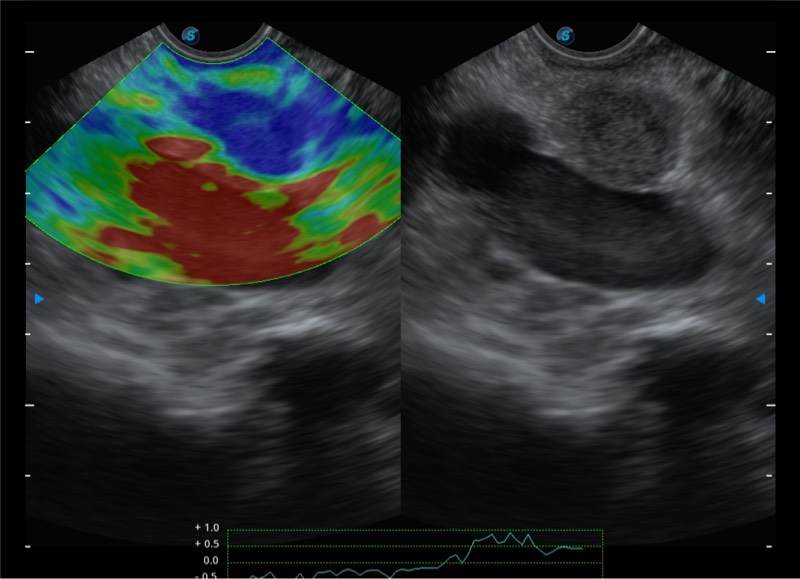

搭载百万级CMOS成像技术

及自主研发凸阵换能器,

可呈现优质的内镜和超声画面

基于二十年的超声技术积累,玖鼎集团提供了最新一代的独立超声主机,在提供高质量图像的同时满足多学科使用。具备常见多普勒技术并提供弹性成像、声学造影等高端影像技术。新一代传感器具有更强的抗干扰能力并减少图像伪影。

4-12MHZ宽频输出